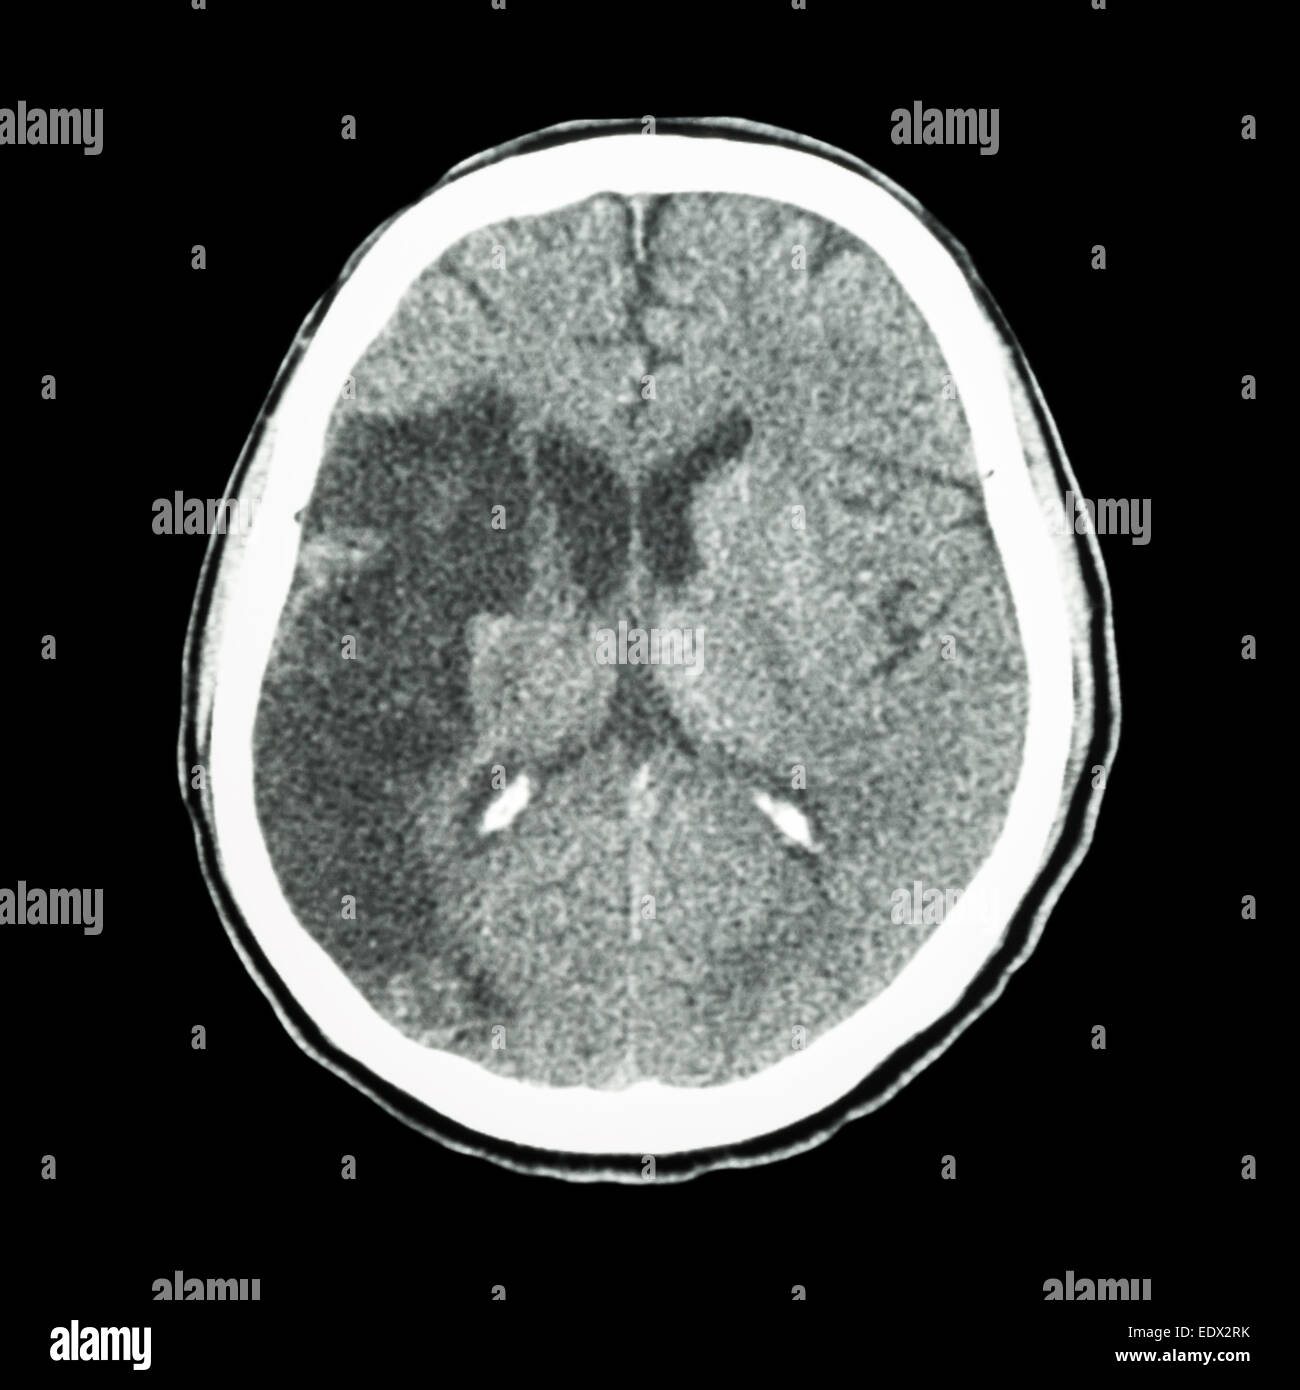

Ct Scan Of Brain Show Ischemic Stroke Or Hemorrhagic Stroke

P 0 08 and placebo treated. During the first week following a cortical infarct hypoattenuation and swelling become more marked resulting in significant mass effect and clear demarcation of the infarct often with. The fogging phenomenon is seen on non contrast ct of the brain and represents a transient phase of the evolution of cerebral infarct where the region of cortical infarction regains a near normal appearance. Ischemic stroke occurs when a vessel supplying blood to the brain is obstructed.

It accounts for about 87 percent of all strokes. Nicht kontrastierte schädel ct s stellen die bildgebung der ersten wahl dar wenn es um die abklärung eines apoplex mit unterscheidung zwischen ischämischem und hämorrhagischem schlaganfall und den ausschluss anderer intrakranieller pathologien geht. Gewöhnlich sind ältere menschen davon betroffen doch auch bei kindern oder jugendlichen kann sich ein hirnschlag ereignen. Mini med studium 19 225 views.